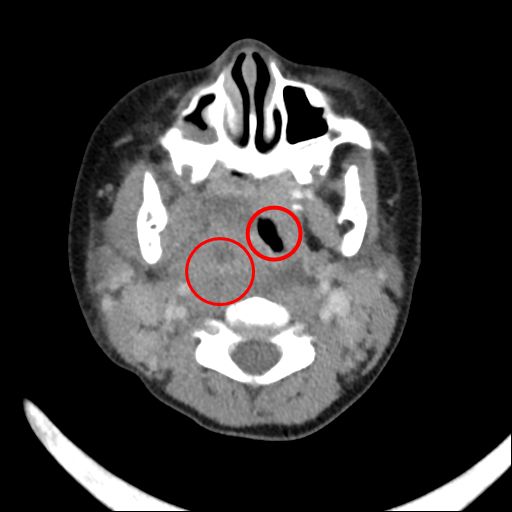

兩歲半的小涵(化名)因持續兩三日的發燒,且不願開口說話、進食,被送往花蓮慈濟醫院就診,檢查發現是深頸部後咽腔膿瘍壓迫所致

,經小兒部張雲傑醫師診斷需盡快動手術,並立刻聯繫耳鼻喉科周昱甫醫師做清創和引流,所幸小涵在術後恢復良好,日前已順利出院。

後咽腔膿瘍是深頸部感染的一種,指病患在後咽處長了一個膿包,並且根據膿的位置及大小會引發不同的症狀;深頸部感染非常危險且致命,常見原因包括上呼吸道感染或食道異物損傷等等,使細菌感染並入侵深頸部筋膜間隙,造成頸部發炎及化膿。花蓮慈院小兒部秦家翊表示,「後咽腔膿瘍在幼兒病症中算是急症之一,若未及時治療,膿瘍壓迫到呼吸道,可能造成急喘以及哮鳴聲的現象,嚴重時甚至會引發呼吸困難。」